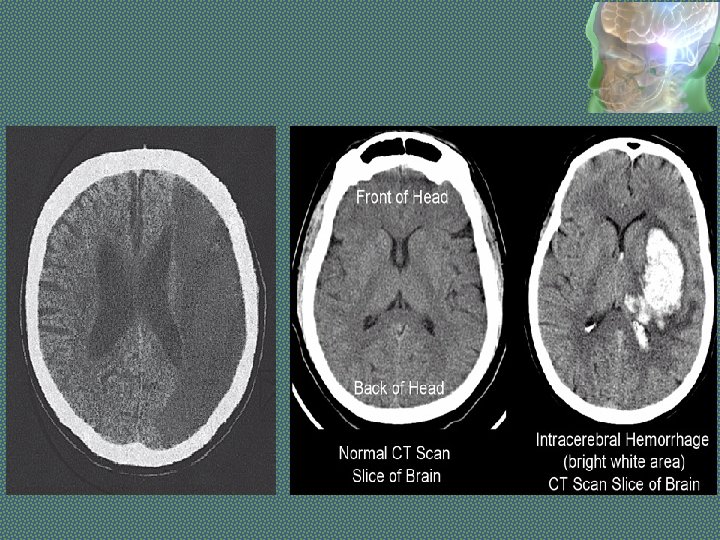

Investigations - STROKE • Imaging in Acute Stroke. • Non-contrast CT: will demonstrate haemorrhage immediately but cerebral infarction is often not detected or only subtle changes are seen initially.